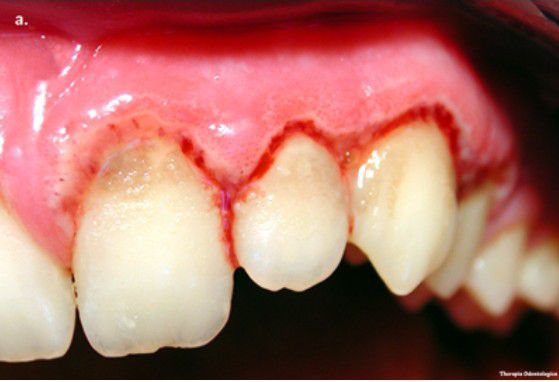

Acute necrotizing ulcerative gingivitis

Acute necrotizing ulcerative gingivitis (ANUG) is a rare infectious disease of the gum tissue, affecting <1% of the population. ANUG presents as an acute, painful, and destructive ulceration and inflammation of the interdental gum tissue